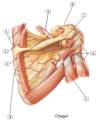

1 - Musculocutaneous nerve (C5-7)

2 - Axillary nerve (C5-6)

3 - Radial nerve (C5-8, T1)

4 - Median nerve (C5-8, T1)

5 - Ulnar nerve (C7-8, T1)

6 - Thoracodorsal (middle subscapular) nerve (C6-8)